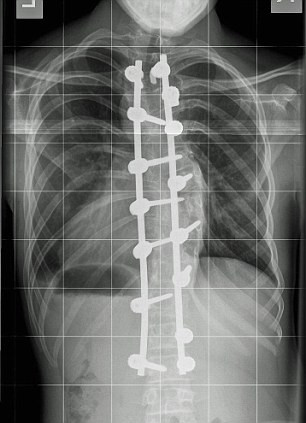

Un adolescent a crescut 12 centimetri peste noapte, dupa o operatie pe care a facut-o la coloana vertebrala.

Harvey Legge, 14 ani, sufera de scolioza, iar curbura cloanei sale era atat de mare, incat ii atingea organele vitale.

Mama copilului spune ca operatia a insemnat un miracol: “Nu pot sa cred… Copilul meu s-a inaltat peste noapte cu 12 centimetri. Este minunat ce s-a intamplat. Este o minune Dumnezeiasca.... ”.

Miracolul despre care povesteste mama baiatului se vede si in radiografiile facute inainte si dupa operatie.